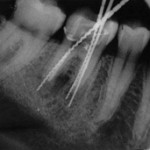

Der Zahn wurde anschließend von einem Kollegen reseziert, der Knochendefekt (Osteolyse) reicht hierbei sehr weit in Richtung Bifurkation. In den folgenden Verlaufskontrollen konnte leider keine knochendichte Ausheilung nachgewiesen werden.

Im Dezember 2007 wurde der bis dahin klinisch unauffällige Zahn wieder perkussionsempfindlich. Im Röntgen imponierte eine deutliche Osteolyse entsprechend einem Rezidiv.

Der Zahn wurde anschließend trepaniert und die alte Wurzelfüllung entfernt. Es konnte dabei bis in den Herd aufbereitet werden.